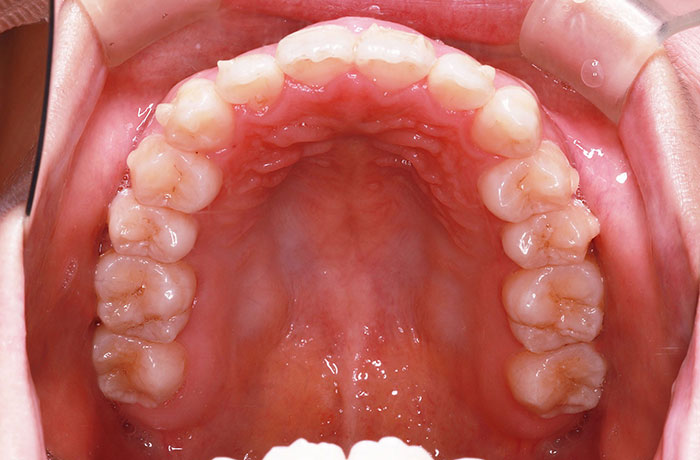

K様

治療前

before

年齢 27歳

性別 女性

治療名称 マウスピース型カスタムメイド矯正歯科装置(インビザライン)・コンプリヘンシブパッケージ(フルパッケージ)

総額治療費用 770,000円(税込10%) 金額備考 精密検査料・診断料 33,000円(税込10%)

治療期間 1年11か月 通院頻度など 40日ごと

1枚につき10日装着を指示しました。

患者の症状 上顎前歯の前突、八重歯

治療方法 上下左右の第一小臼歯抜歯で、マウスピース型カスタムメイド矯正歯科装置による矯正

治療結果 上顎前歯の前突、八重歯が改善されました。

歯並びをより良くするために追加でアライナーを発注しました。

リスク/副作用 決められた時間装着する必要があります。